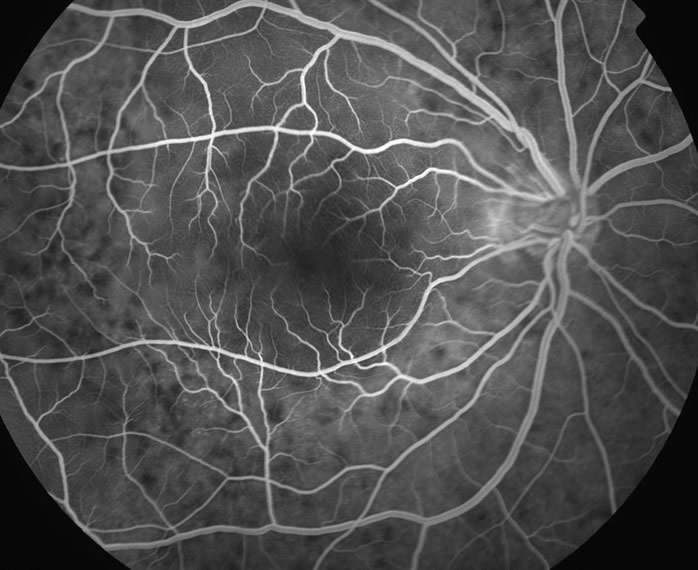

FAの初期像1

急性期の原田病症例におけるFA初期像。多発するdark spotが観察できる。

出典

img

1: 大黒伸行先生ご提供